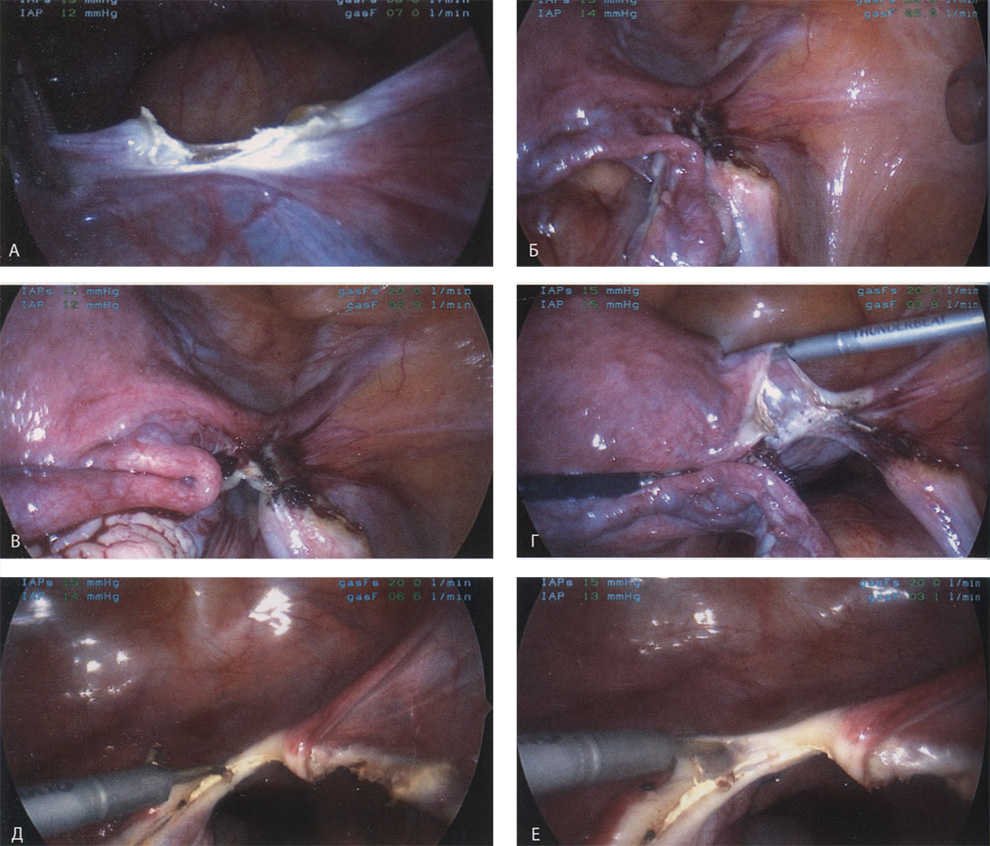

Если оставить в стороне эти достоинства и недостатки, то техника лапароскопической гистерэктомии фактически идентична технике лапаротомической гистерэктомии. В самом начале операции, если она выполняется лапароскопическим методом, необходимо осмотреть всё операционное поле, воспользовавшись для этого панорамным обзором (рис. 12-33—12-37). Операцию начинают с коагуляции и пересечения круглых связок, чем обеспечивается доступ к широкой связке (рис. 12-38—12-40). Брюшину, переходящую с купола мочевого пузыря на переднюю поверхность матки, вскрывают. Пузырь отсепаровывают от матки острым путём (рис. 12-41). После этого вскрывают задний листок широкой связки, а затем принимают решение, оставлять или удалять яичники. Если принято решение оставить яичники, то коагулируют и пересекают собственные связки яичников и маточные трубы (рис. 12-42). Если принято решение удалить яичники (то есть выполнить сальпингоофорэктомию), то с обеих сторон выполняют диссекцию мочеточников от воронко-тазовых связок, которые затем отсепаровывают, коагулируют и пересекают (рис. 12-43). Затем ткань широкой связки отделяют от маточных сосудов (отпрепаровывая их), изолировав, таким образом, мочеточники от маточных сосудов (рис. 12-44 А). Восходящие ветви маточных сосудов коагулируют справа и слева, а затем пересекают (рис. 12-44 Б, В).

Коагулируют и пересекают так называемые поддерживающие связки матки (рис. 12-44 Г, Д). Возможно, потребуется разделить ткани, соединяющие мочевой пузырь с передней стенкой влагалища. После этого вскрывают влагалище и коагулируют все кровоточащие сосуды. Если хирург владеет методами лапароскопического наложения швов, то он зашивает культю влагалища. Предварительно матку извлекают через влагалище или путём морцелляции (рис. 12-45 и 12-46).

Рис. 12-38. А. Круглая связка коагулирована и рассечена. Разрез продолжен на широкую связку. Б. Вскрыта правая широкая связка. В. Коагулирована правая круглая связка. Г. Справа рассечена складка брюшины мочевого пузыря. Д. Коагулированы и пересечены левая круглая связка, маточная труба и собственная связка яичника. Е. Увеличенное изображение Д.